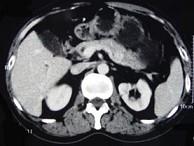

问题 貌似健康而有自发性空腹或运动后低血糖症的原因中最常见的是() {图1}

选项 A.药源性低血糖症 B.胰岛素瘤 C.反应性低血糖 D.胰岛素自身免疫综合征 E.伴瘤的低血糖

答案 B